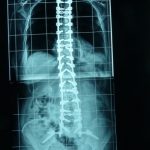

Εικ. 2: (α,β) Προεγχειρητικές ακτινογραφίες της Σ.Σ. Προσθί-οπισθία και Πλαγιά, σε όρθια στάση.

Παρατηρείται ύπαρξη μεγάλης σκολιώσεως και κυφώσεως η οποίες έχουν οδηγήσει σε πλήρη αστάθεια και ανισορροπία του κορμού.

(γ,δ) Μετεγχειρητικές ακτινογραφίες της Σ.Σ. Προσθί-οπισθία και Πλαγιά, σε όρθια στάση.

Η ασθενής υποβλήθηκε σε χειρουργική επέμβαση για την αποκατάσταση της ισορροπίας του κορμού της και την εξάλειψη της παραμορφώσεως της Σ.Σ. Για το σκοπό αυτό έγινε σπονδυλοδεσία από τον 3ο θωρακικό σπόνδυλο μέχρι τα λαγόνια οστά.